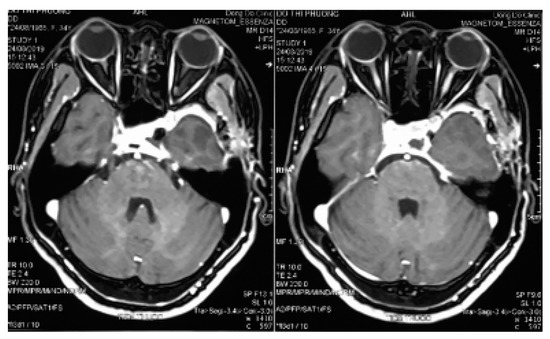

A 34-year-old female presented with a history of occassional headache without remarkable physical and neurological symptoms. Routine laboratory investigations and pituitary hormonal tests were all normal. She was taken for a magnetic resonance imaging and a mass was discovered in the region of the sellar and left parasellar. The size of the lesion was around 30 mm. It elicited a high signal on T1-weighted and T2-weighted images, strong enhanced gadolinium, and a homogenous intense surrounding left cavernous internal carotid, pushing downward on the skull base and pushing the pituitary contralaterally (Figure 1).

Figure 1.

Contrast-enhanced magnetic resonance imaging examination of the brain. (a,b) Pre contrast coronal and sagital T1w showed an extra axial sellar and left parasellar mass with hyperintensity, the cavernous internal carotid artery is pushed inferiorly and encased by the lesion. (c) Coronal T2w showed a high signal intensity of the mass. (d) Initial gadolinium-enhanced axial T1w showed heterogenous enhancement of the mass.

In the magnetic resonance imagings, the lesion revealed an enhanced homogenous mass encircling the cavernous segment of the internal carotid artery without occluding it. This might be related to the natural character of the tumor. With cavernomas in the cavernous sinus, the blood stream through the lesion was homogenous, contrary to cavernomas intracerebral parenchyma, with no bleeding inside the tumor, and no calcification. Cerebral cavernomas appeared as “popcorn-shaped” or “berry-shaped”, which showed isointense in magnetic resonance imagings with a rim of signal loss due to hemosiderin. This was a specific radiological feature of parenchymal cavernomas, but it seldom happens with extra axial cavernomas, especially in the cavernous sinus [7]. In the magnetic resonance imaging, CSCs were homogenous; hyperintense in T1w, T2w, and T2 Flair; showed contrast enhancement; and rarely had intratumor bleeding or calcification (Figure 1).